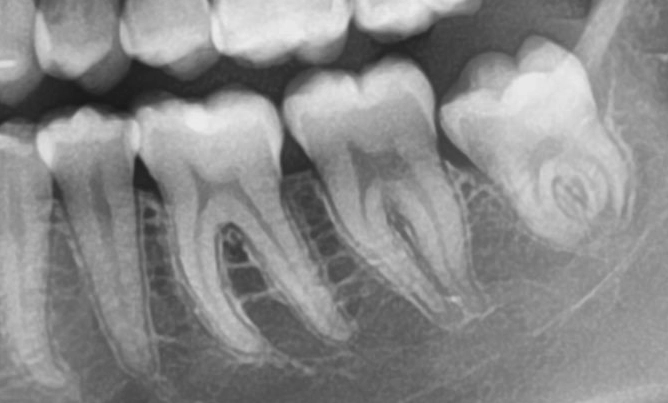

Tand anatomie

Glazuur (Emaille)

Dit is de harde buitenlaag van je tand (of kies). Het is het hardste spul in je hele lichaam, nog harder dan bot! Het beschermt je tand tegen alles wat je eet of drinkt. Maar als je te veel suiker eet en niet goed poetst, kan het glazuur kapot gaan (gaatjes = cariës).

Dentine

Onder het glazuur zit het dentine (of tandbeen). Dit is minder hard dan glazuur, maar nog steeds stevig. Het zit vol met hele kleine kanaaltjes (die heten tubuli — daarover zo meer). Dentine is gevoeliger: als je glazuur beschadigd is, voel je vaak pijn via het dentine.

Pulpa (Tandzenuw & Bloedvaatjes)

In het midden van de tand zit de pulpa. Dit is het zachte gedeelte met:

- Zenuwen: die geven pijn door als er bijvoorbeeld een gaatje is.

- Bloedvaatjes: die zorgen ervoor dat de tand voedingsstoffen krijgt.

Als de pulpa ontstoken raakt, kan een wortelkanaalbehandeling nodig zijn.

Tubuli (Dentinekanaaltjes)

In het dentine zitten hele kleine buisjes: de tubuli. Ze lopen van buiten naar binnen en geven signalen (zoals kou of warmte) door naar de zenuw. Daarom kun je bijvoorbeeld kiespijn voelen bij iets kouds. Of gevoelige tanden ervaren als de beschermlaag weggepoetst is.

Cementlaag

Rond de wortels van de tand zit een laagje cement. Dit is niet hetzelfde als bouwcement, maar het helpt de tand stevig in het kaakbot te verankeren. Hieraan hechten de vezels van het ligament.

Parodontaal ligament

Dit zijn kleine vezeltjes (soort elastiekjes) die de tand verbinden met het kaakbot. Ze zorgen dat de tand niet te strak vast zit, maar een beetje kan meebewegen bij het kauwen. Net als een schokdemper van een auto. Implantaten hebben dit niet.

Tandvlees (Gingiva)

Het tandvlees bedekt het kaakbot en beschermt de wortels. Gezond tandvlees is roze, stevig en bloedt niet als je poetst.